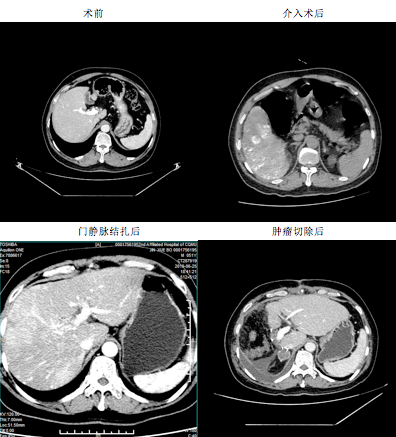

5月28日,在江南院区重庆市目前最先进的杂交手术室,刘作金教授首先对金先生的右肝癌灶做了介入栓塞治疗,随即在腹腔镜下行门静脉右支结扎术。这种改良的手术方式,不仅可有效控制肿瘤进一步发展,又能促进左半肝代偿性增生。6月25日,CT复查结果提示金先生的左半肝明显增生。刘作金教授团队于7月1日完成了治疗的第二步腹腔镜下的右半肝切除术,术后病理提示肝细胞肝癌,术后仅仅7天,金先生康复出院。